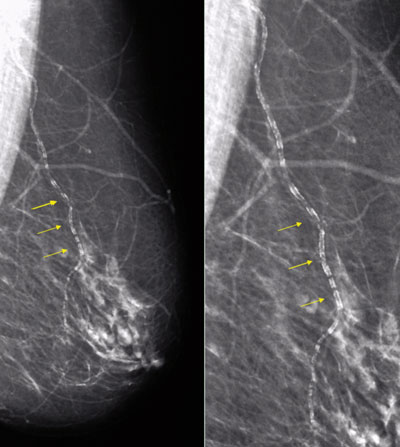

La presencia de calcificaciones arteriales mamarias (CAM) (Figura 1) ha sido descrita desde hace largo tiempo, pero su valor como índice de enfermedad aterosclerótica sistémica no había sido estudiado en forma sistemática. Se ha estimado que 12,7% de las mujeres sometidas a cribaje de cáncer de mama con mamografía tiene algún grado de calcificación arterial, que se incrementa a 60%-70% en mayores de 70 años o portadoras de enfermedad renal crónica1. Sin embargo, existen diferencias morfológicas y fisiopatológicas entre las CAM y las calcificaciones, que se observan en la enfermedad aterosclerótica coronaria o carotídea, que no permiten considerarlas equivalentes. Las calcificaciones coronarias, con demostrado valor diagnóstico para aterosclerosis subclínica, asientan sobre la íntima arterial, mientras que las detectadas en la mamografía asientan sobre la capa media (denominada arteriosclerosis de Mönckeberg). Esta localización les da un aspecto radiológico peculiar cuando son severas, que se ha denominado en riel o vía de tren (tramway-track).